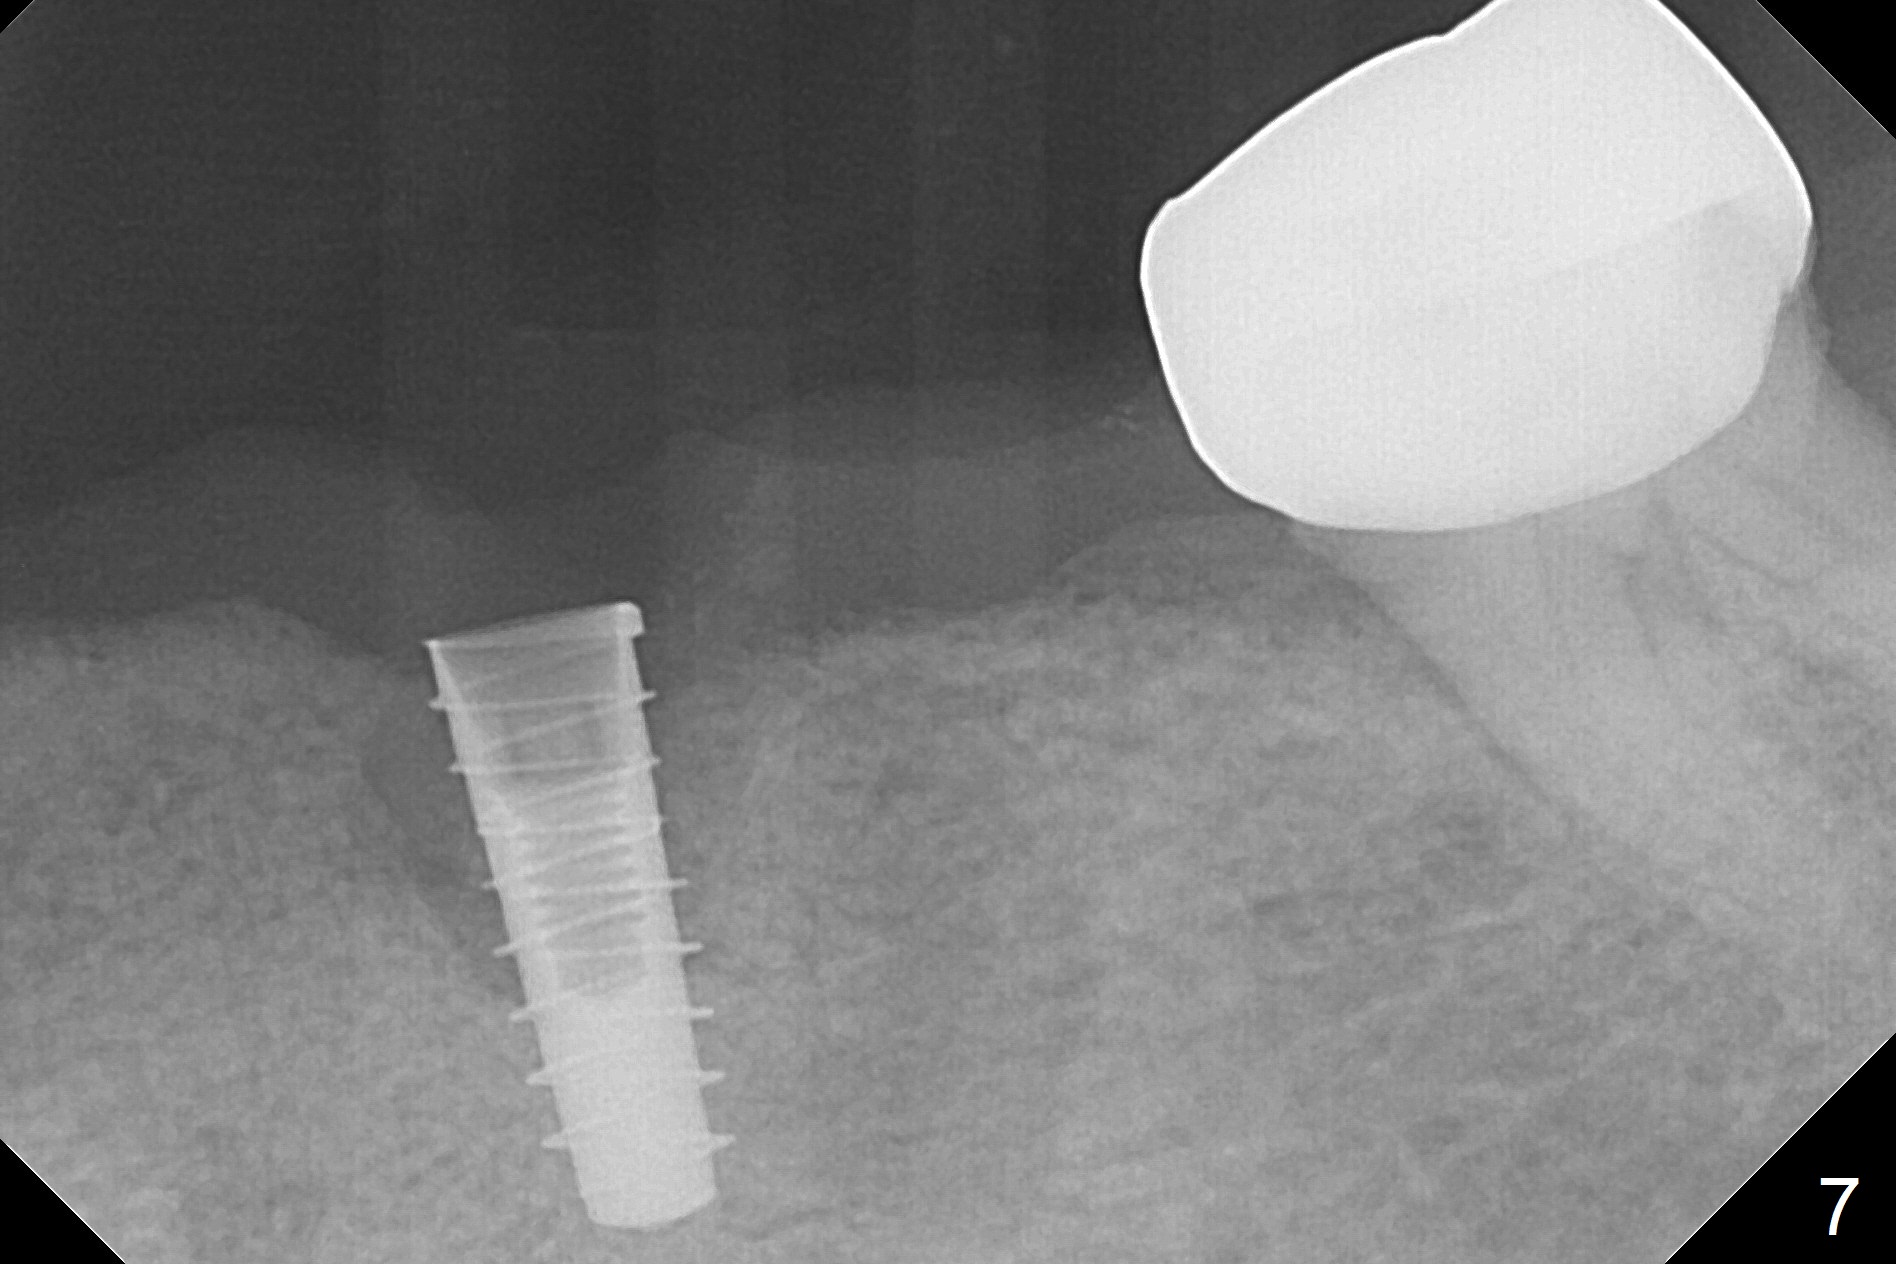

After removal of the pontic at #19 and retainer at #20 (Fig.1) and of vertically fractured root, the buccal plate is found to be defective (Fig.2 *). An implant will be placed as lingual as possible. Since the apex of the affected tooth is coronal to the Mental Loop (Fig.3 red dashed line), an osteotomy (Fig.4 yellow arrow) to be established in the mesial slope (blue dashed line) after extraction (black area) appears to be safer than that along the long axis of the tooth. The initial osteotomy is accomplished by free hand (Fig.5), but when the lower RPD is inserted, the superior end of the 1.5 mm pilot drill is distal (Fig.6). When the trajectory is corrected using the RPD as a surgical guide at the same depth (17 mm gingival level), brisk hemorrhage is from the osteotomy without severe pain. After hemostasis is achieved by packing the socket with Osteogen plug and bone graft and packing bone graft into the osteotomy, 3.3 mm Magic Drill is used for 14 mm. A 4x11 mm IBS implant is placed with 60 Ncm (Fig.7). The implant is then placed deeper, followed by placement of a 4.5x4(3) mm abutment and further bone graft (Fig.8). Finally the implant/abutment complex is apparently in an acceptable mesiodistal position with a large buccal gap which has been filled by bone graft (Fig.9 *). In fact the Mental Loop seems to have been not violated in the procedure (Fig.10). X-ray is taken 3 and 6 months postop. Bone graft (Fig.11,12 (CBCT) *) appears to remain over the buccal (B) surface of the implant coronally 13 months postop (7 months post cementation). The gingiva at #19 and 20 is apparently healthy 8 months post cementation except mild recession at #20 (Fig.13).